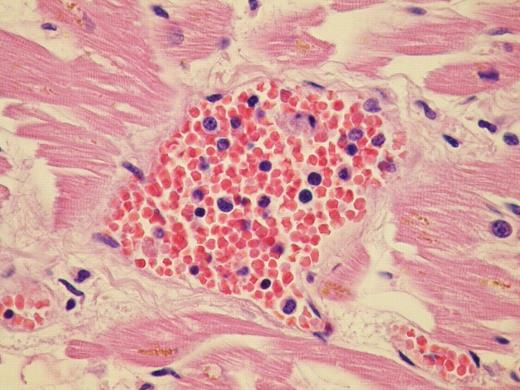

Primary myelofibrosis is a chronic myeloproliferative disease characterized by connective tissue deposition in the bone marrow and extramedullary hematopoiesis commonly involving the liver and the spleen.

We report the case of a 60 year old patient with advanced Post Thrombocitemia Myelofibrosis extensively localized in almost all organs. He was referred to our Center in April 2008; clinical, radiological and haematological features suggested an evolution into Myelofibrosis. Molecular analysis for V617F JAK2 mutation was negative. Hemogram showed leukocytosis, mild anemia and normal platelet count. After few months of treatment with Danazol and Thioguanine, he was admitted for hemodynamic failure; echocardiography and chest X-ray were normal; abdomen CT scan confirmed important splenomegaly and didn't show any deep thrombosis. During hospitalization he developed massive intracerebral haemorrhage, cause of death. Post mortem histopatological examination documented osteomyelosclerosis and wide localization of extramedullary hematopoiesis. Morphological examination of the specimens showed an extensive dissemination of megakaryocytes, erythroid and myeloid precursors immunoreactive with factorVIII, hemoglobin, and myeloperoxidase respectively. We documented intravascular involvement of spleen, liver, lymph nodes, lungs, adrenal glands, myocardium, and central nervous system. Noteworthy fibrosis associated with haematopoietic cells were broadly distributed into retroperitoneal tissue.